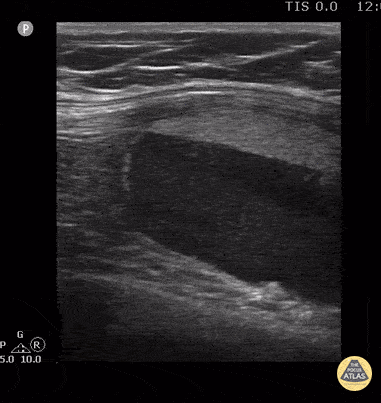

15 year old female with patella fracture after a fall. Note the large suprapatellar effusion with discrete layering of the echogenic marrow/adipose above the acute hypoechoic blood. The lipohemarthrosis is visible in long and short axis (images 2 and 3 of case series). Contributor: Antonio Riera, MD Yale University School of Medicine